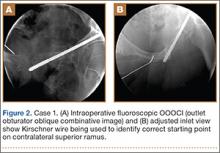

A C-arm fluoroscopy unit (Ziehm, Orlando, Florida) was positioned on the injured side. The surgeon stood on the contralateral side. A pelvic OOOCI (outlet obturator oblique combinative image) of the symphysis pubis was obtained. This view defined the medial and lateral extents of the inferior ramus. A 0.062-in smooth Kirschner wire was used to percutaneously locate an ideal starting point on the cranial aspect of the contralateral superior pubic ramus. The starting point was adjusted on this view until an ideal intended trajectory into the contralateral (affected) inferior pubic ramus was visualized (Figure 2A).

The C-arm beam was then oriented to an “excessive” pelvic inlet view tangential to the posterior cortical surface of the affected inferior pubic ramus (Figure 2B). The tip of the wire was then adjusted to position and aim it slightly anterior to the posterior cortical surface of the affected inferior ramus. The wire was advanced into the bone about 1 cm, and the location and direction of the wire were reconfirmed as accurate.